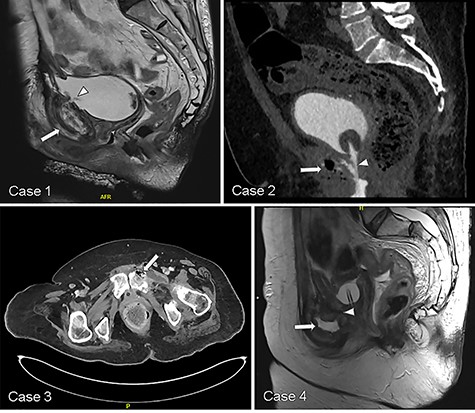

We identified four women, median age 66 (IQR 4.5) years old, who underwent USF management within a narrower period of August 2017 and May 2019 (Table 1). Three patients presented with pubic pain and all were diagnosed with USF on CT or MRI (Table 2). Pubic edema, enhancement and erosion were common features suggesting osteomyelitis associated with the fistulas (Fig. 1). Patients ultimately underwent extirpative surgery with urinary diversion, bone debridement/resection and tissue interposition. All were confirmed to have pubic osteomyelitis on histology (Table 2).

Representative CT and MRI imaging demonstrating USF (white arrowhead) and features suggesting pubic osteomyelitis (white arrow) in each respective case.